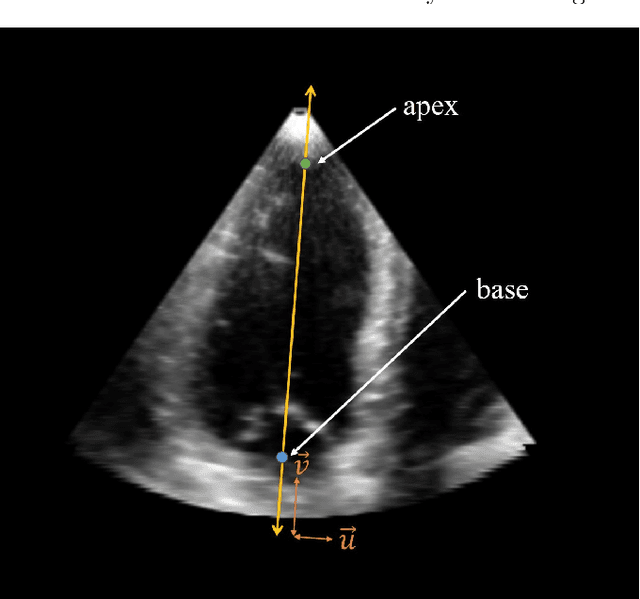

Abstract:The perfect alignment of 3D echocardiographic images captured from various angles has improved image quality and broadened the field of view. This study proposes an accelerated sequential Monte Carlo (SMC) algorithm for 3D-3D rigid registration of transthoracic echocardiographic images with significant and limited overlap taken from apical window that is robust to the noise and intensity variation in ultrasound images. The algorithm estimates the translational and rotational components of the rigid transform through an iterative process and requires an initial approximation of the rotation and translation limits. We perform registration in two ways: the image-based registration computes the transform to align the end-diastolic frame of the apical nonstandard image to the apical standard image and applies the same transform to all frames of the cardiac cycle, whereas the mask-based registration approach uses the binary masks of the left ventricle in the same way. The SMC and exhaustive search (EX) algorithms were evaluated for 4D temporal sequences recorded from 7 volunteers who participated in a study conducted at the Mazankowski Alberta Heart Institute. The evaluations demonstrate that the mask-based approach of the accelerated SMC yielded a Dice score value of 0.819 +/- 0.045 for the left ventricle and gained 16.7x speedup compared to the CPU version of the SMC algorithm.

Abstract:Purpose: Echocardiography is commonly used as a non-invasive imaging tool in clinical practice for the assessment of cardiac function. However, delineation of the left ventricle is challenging due to the inherent properties of ultrasound imaging, such as the presence of speckle noise and the low signal-to-noise ratio. Methods: We propose a semi-automated segmentation algorithm for the delineation of the left ventricle in temporal 3D echocardiography sequences. The method requires minimal user interaction and relies on a diffeomorphic registration approach. Advantages of the method include no dependence on prior geometrical information, training data, or registration from an atlas. Results: The method was evaluated using three-dimensional ultrasound scan sequences from 18 patients from the Mazankowski Alberta Heart Institute, Edmonton, Canada, and compared to manual delineations provided by an expert cardiologist and four other registration algorithms. The segmentation approach yielded the following results over the cardiac cycle: a mean absolute difference of 1.01 (0.21) mm, a Hausdorff distance of 4.41 (1.43) mm, and a Dice overlap score of 0.93 (0.02). Conclusions: The method performed well compared to the four other registration algorithms.